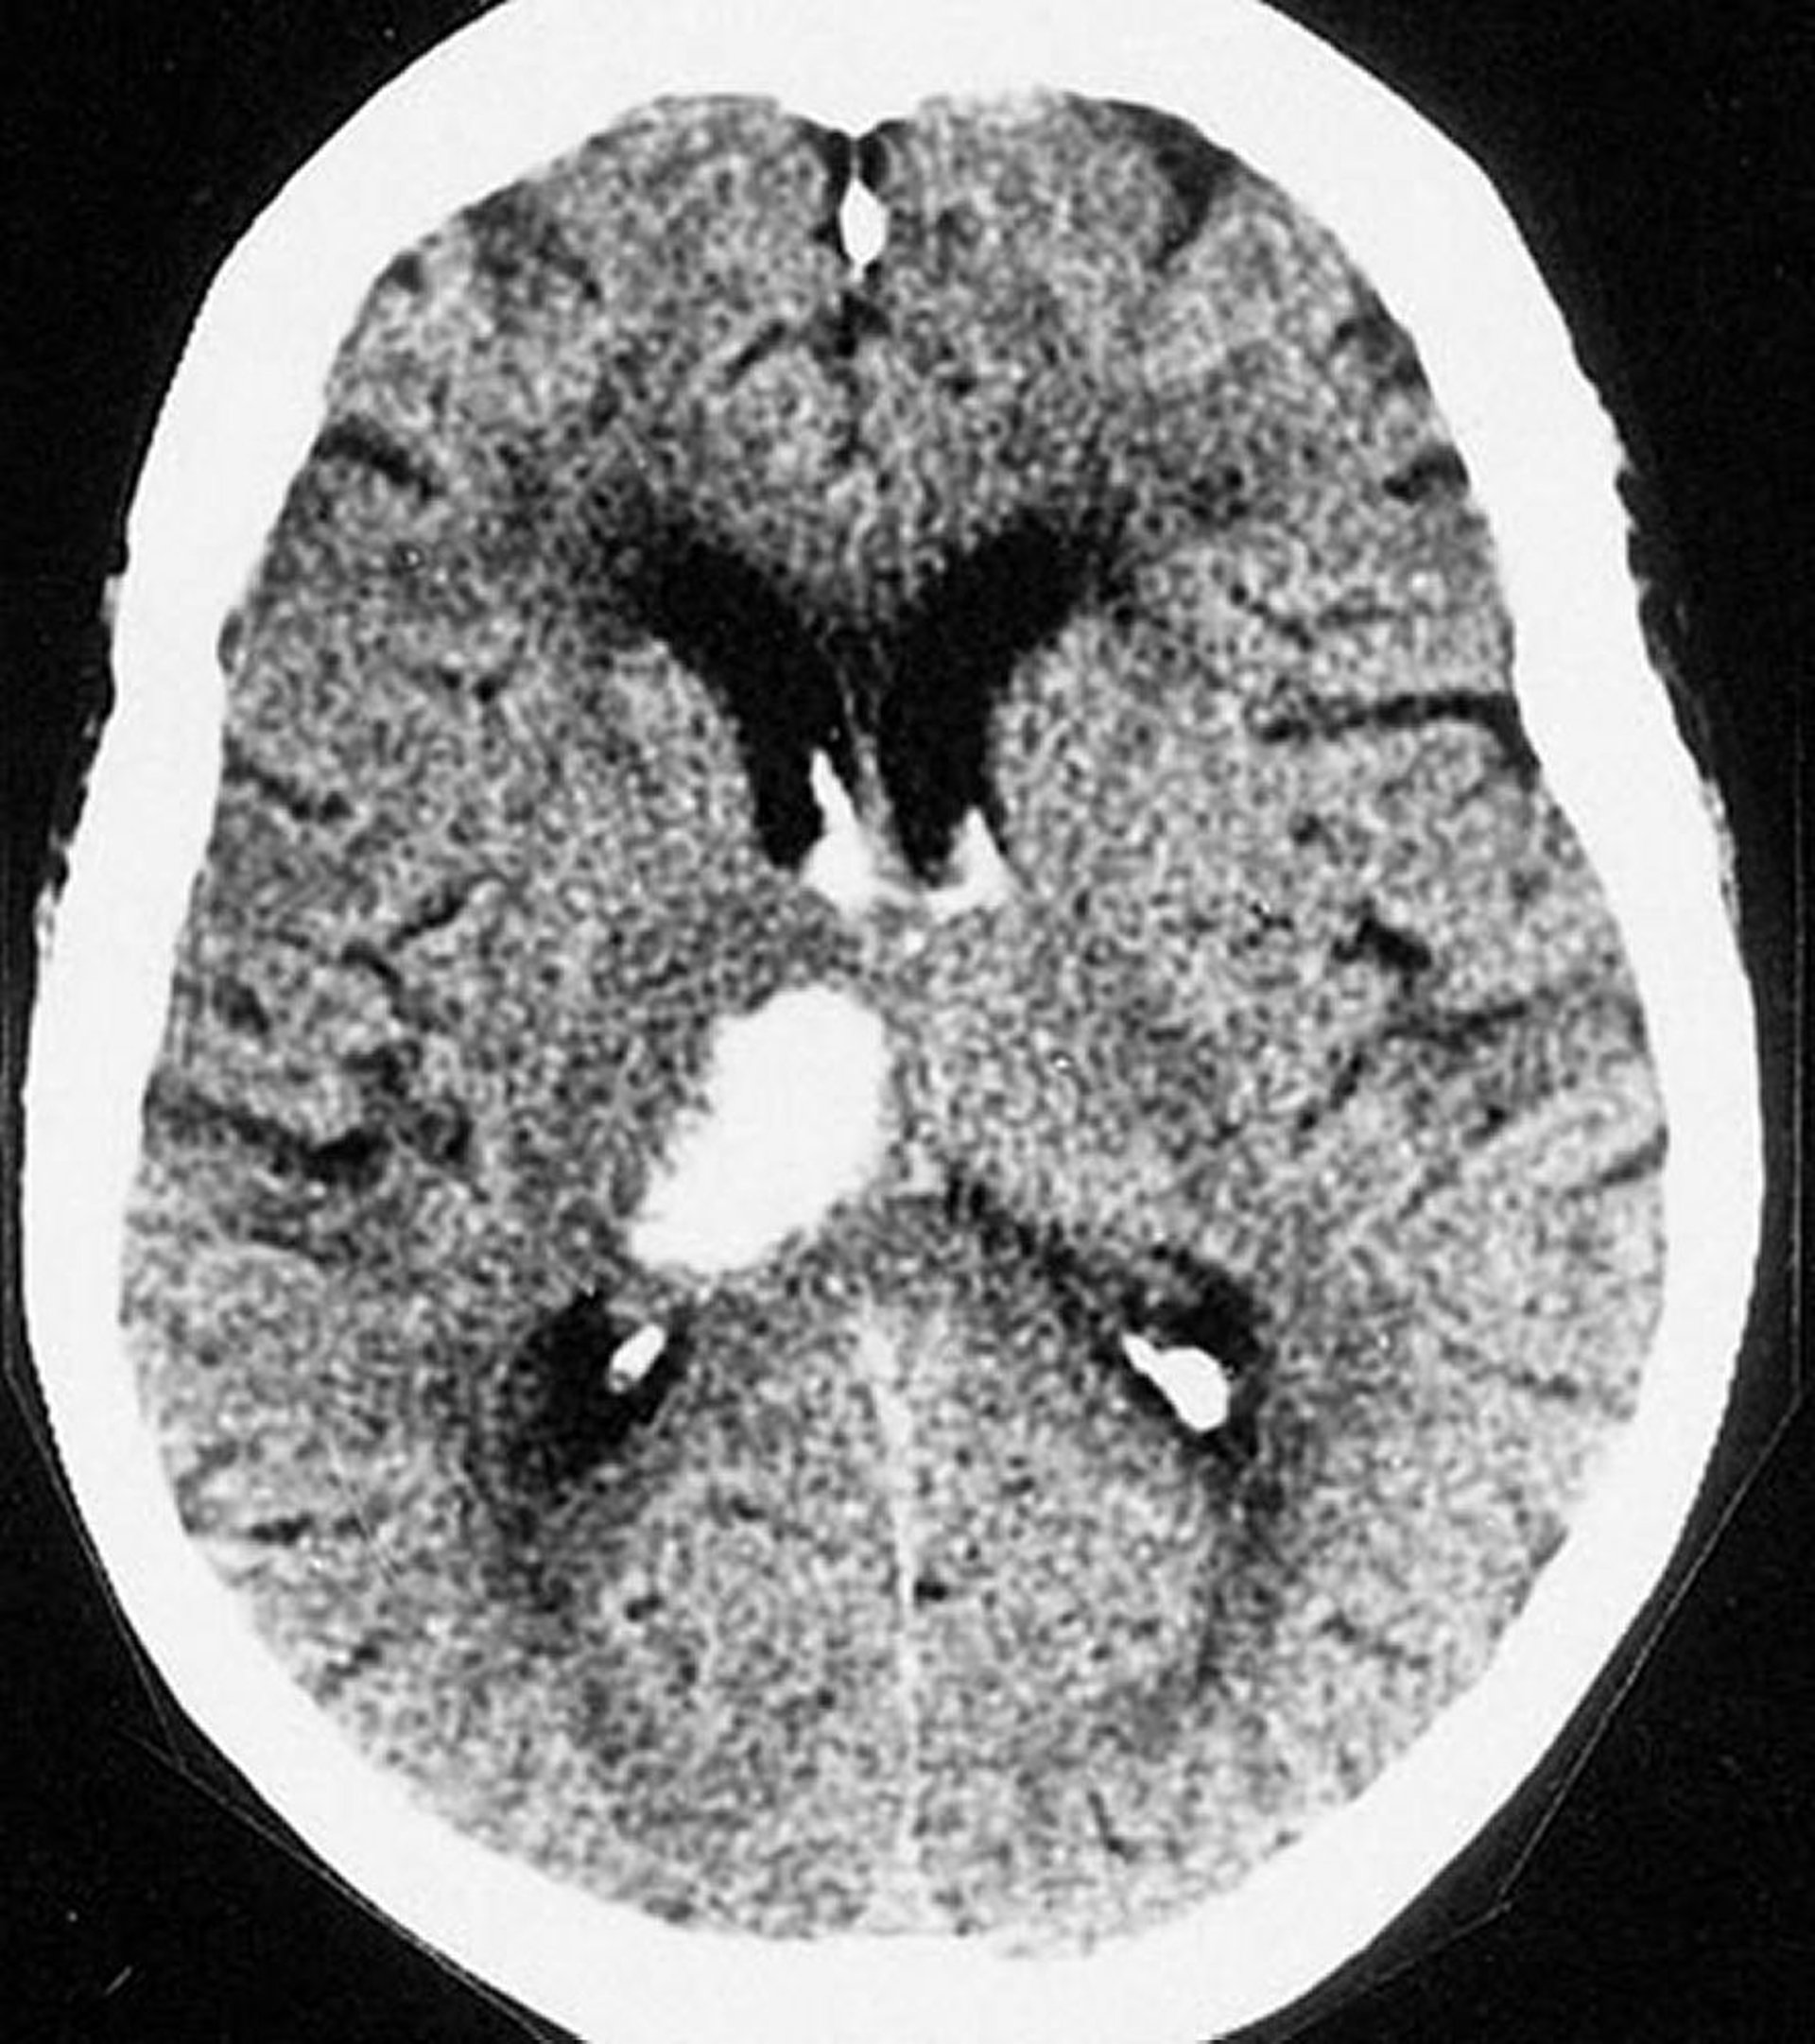

Xuất huyết trong não vùng đồi thị

Phim chụp CT này cho thấy xuất huyết ở đồi thị. Xuất huyết nội sọ thường xảy ra ở đồi thị và trong hạch nền.

Được sự cho phép của nhà xuất bản. Theo Furie K và cộng sự. Trong Atlas of Clinical Neurology. Biên tập bởi RN Rosenberg. Philadelphia, Current Medicine, 2002.